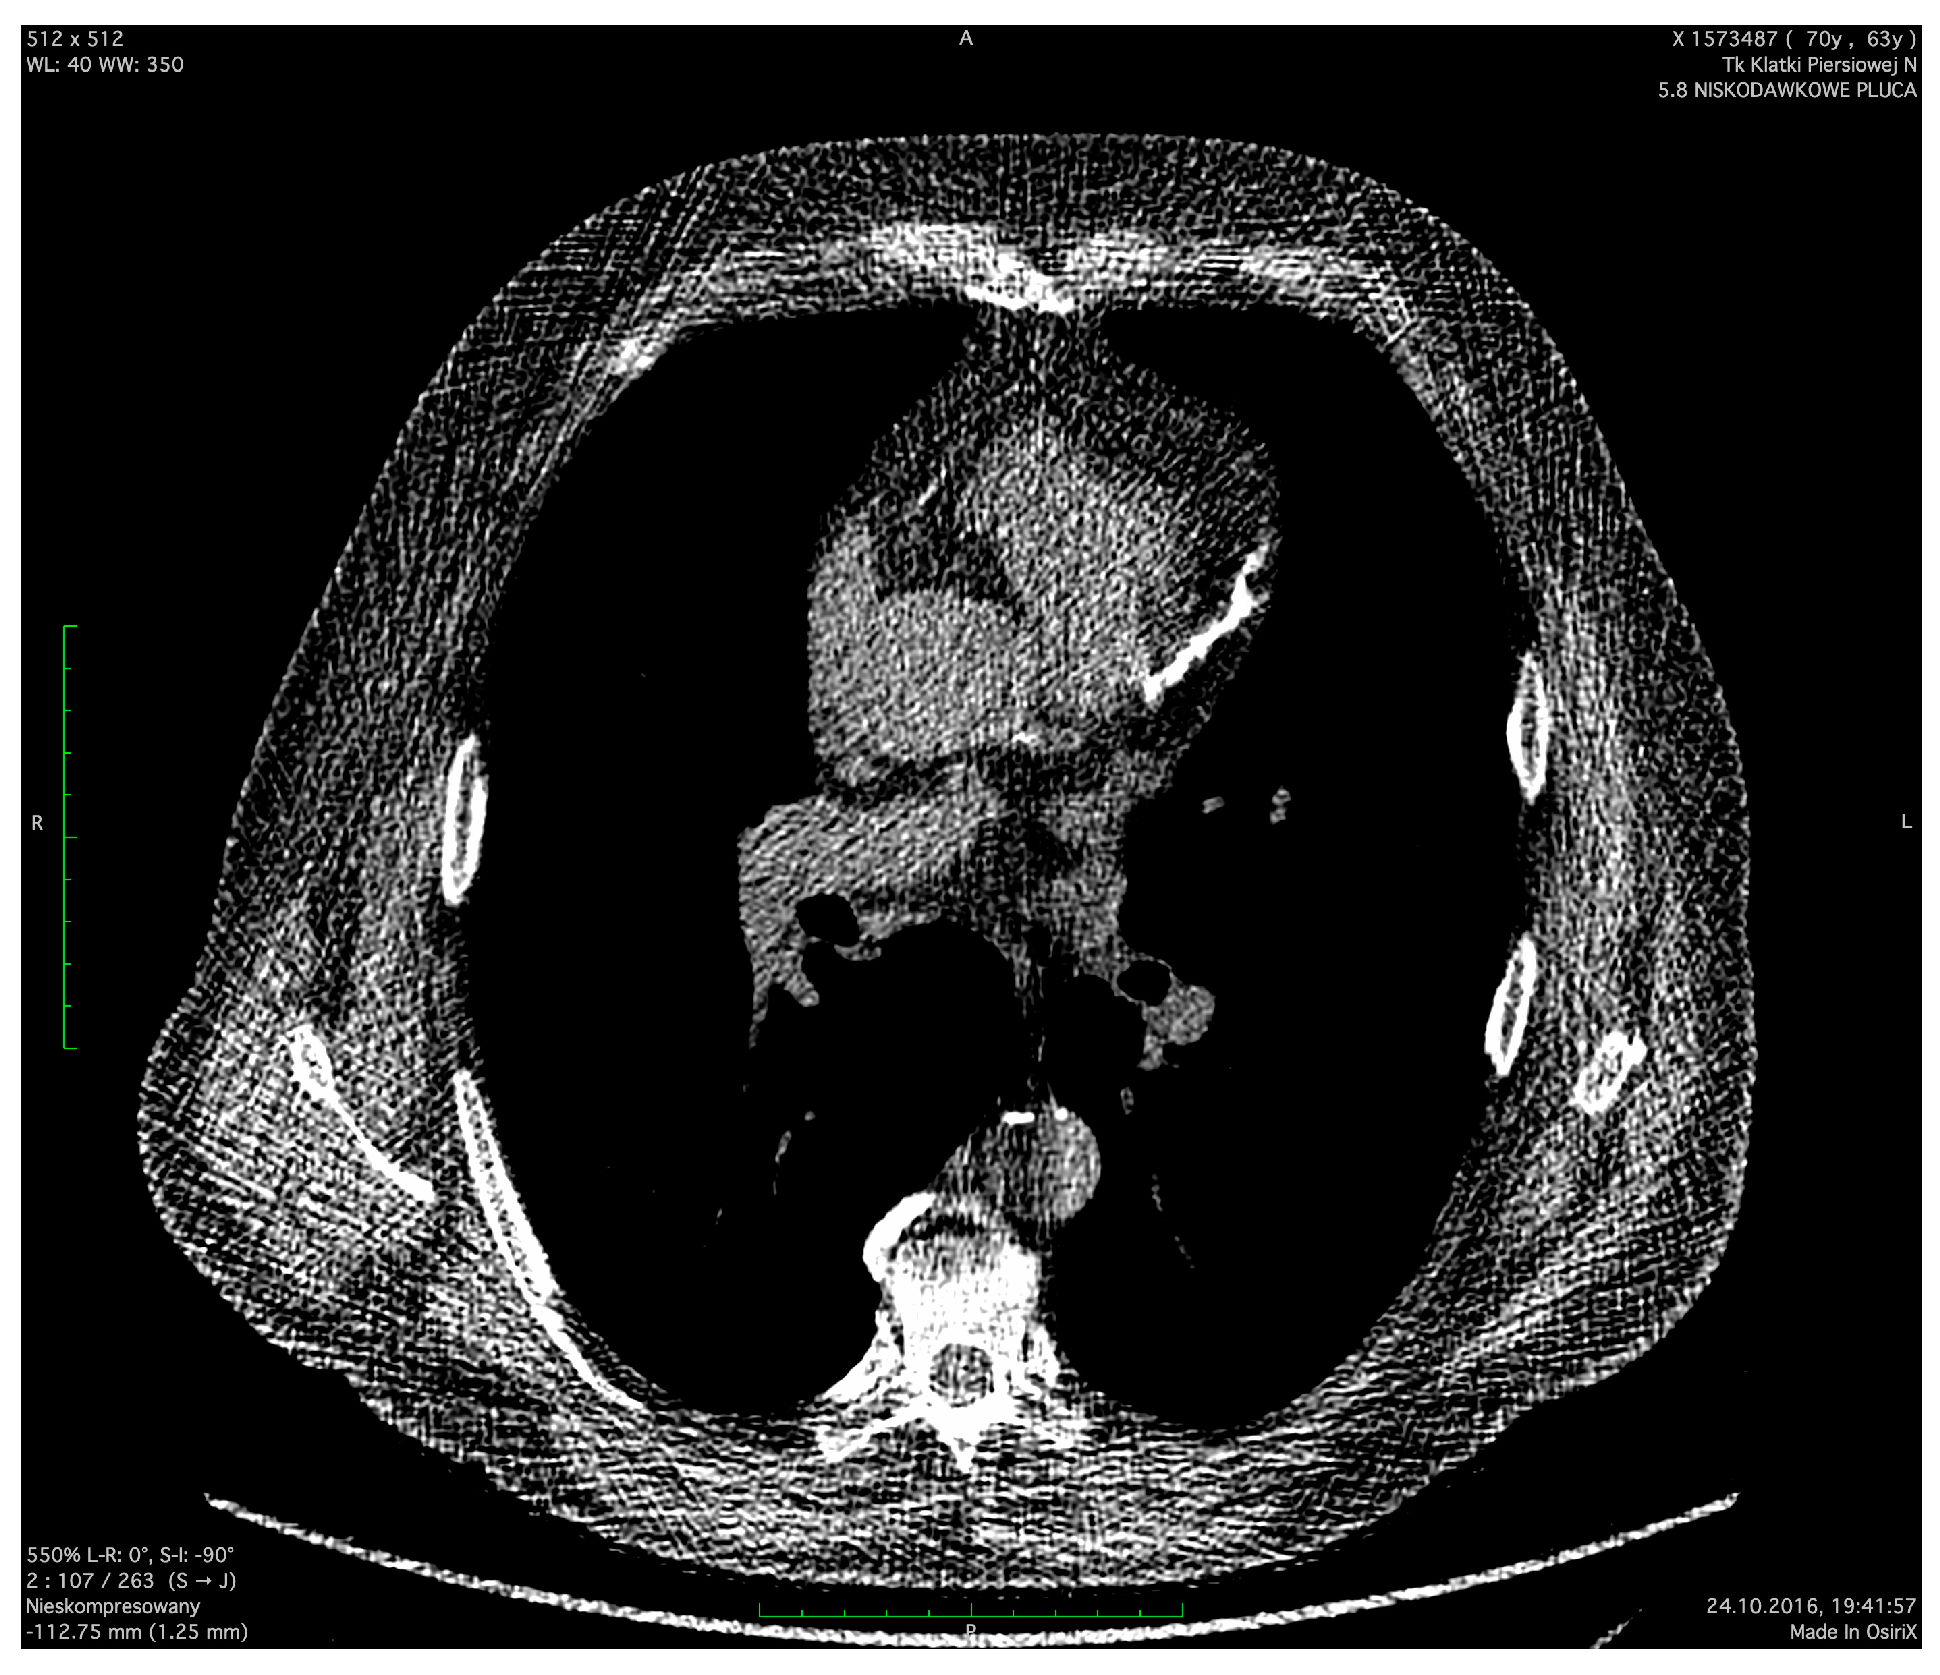

| CAC | ||||

|---|---|---|---|---|

| 0 | 1–3 | 4–6 | 7–12 | |

| Number of observations (n) | 214 (53%) | 106 (26%) | 48 (12%) | 36 (9%) |